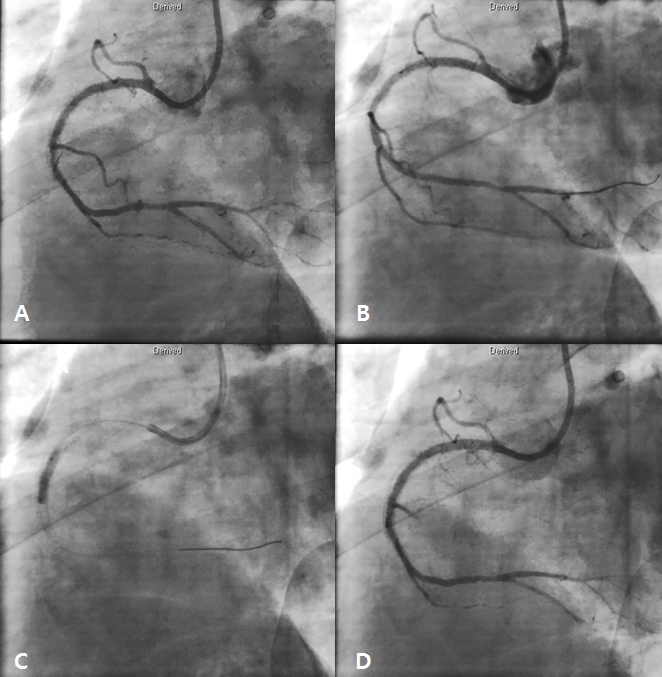

After 3 days later, we performed 2nd stage PCI for proximal LAD. CAG reveled moderate stenosis in proximal LAD (Figure 4A), so we examined optical coherence tomography (OCT) for further evaluation. It showed large amount of plaque (minimal lumen area [MLA] 2.62 mm2) (Figure 5A and 5C). We directly implanted 3.25 and 18 mm everolimus-eluting stent (Xience Alpine®), but follow-up CAG showed mild under-expansion, so we did additional ballooning using 3.25 x 10mm non-complaint balloon (Figure 4B and 4C). Follow-up OCT and CAG showed good distal flow without significant residual stenosis. (post-PCI cross sectional area [CSA] 6.65 mm2) (Figure 4D, 5B and 5D). Because of no-reflow phenomenon for RCA in previous PCI, we performed follow-up CAG and OCT for RCA. CAG and OCT showed stent underexpansion with neointima rupture and large amount of residual thrombi in mid RCA (MLA 2.39 mm2) (Figure 6A, 6B, 7A and 7C). So we did ballooning using 3.25 x 10 mm non-complaint balloon for mid RCA (Figure 6C). Follow-up CAG and OCT showed good distal flow without significant residual stenosis. (CSA 5.03 mm2) (Figure 6D, 7B and 7D). He was discharged without any complications.

Figure 4. Staged procedure for left anterior descending artery (LAD). Coronary angiography (CAG) revealed moderate stenosis in proximal LAD (A). A 3.25 x 18 mm everolimus-eluting stent was implanted (B). There was mild underexpansion in LAD stent (C). Final CAG showed good distal flow without significant residual stenosis after additional ballooning using non-complaint balloon (D).